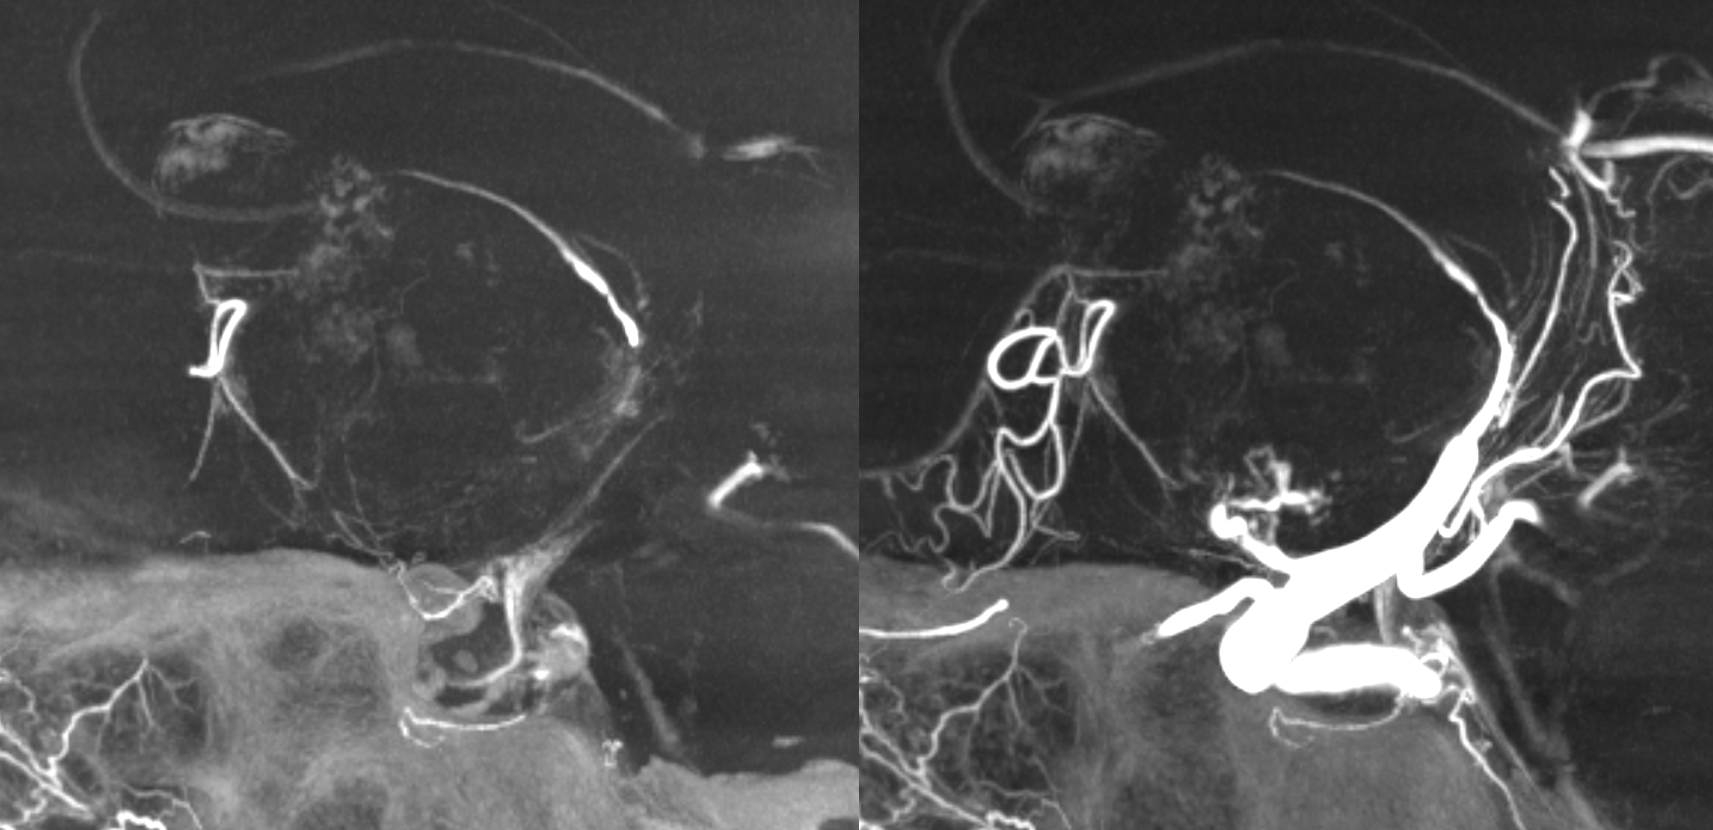

Case 2 — Giant MCA Aneurysm Link to Full Case

Vasa Vasorum (arrow and oval) origin from the MCA just proximal to neck

See full case link for treatment details — below is end result — coils occlude aneurysm and extend to parent vessel to close vasa vasorum also